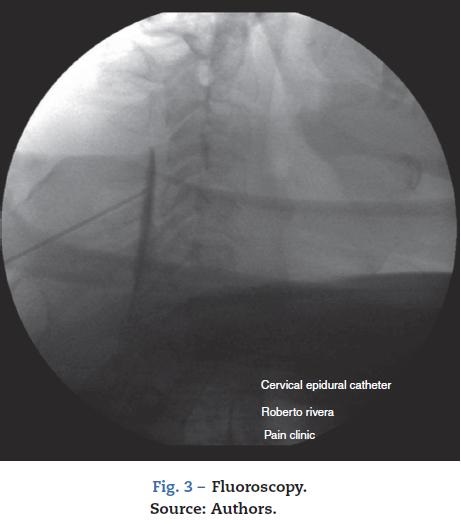

1. Epidural steroids under basic monitoring, intravenous sedation and local anesthesia, and fluoroscopic guidance. The patient was placed in prone decubitus and the epidu-ral space at the level of C4/C5 was located (Fig. 2) using the epidural needle and the loss-of-resistance technique with saline solution. It was confirmed with 0.5 mL of contrast medium (omnipaque 300 mg/mL), followed by 40 mg of methylpredinisolone acetate +1 mL of 0.75% levobupiva-caine + 2mL of 0.9% saline solution (0.9% SS) (Fig. 3)